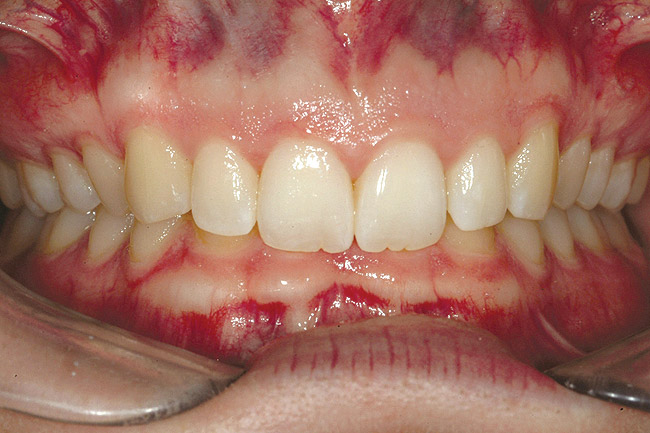

Fig 6 (and Fig 7). Prerestorative orthodontics was completed in 5 months. Final result 3 years, 4 months after completion.

Figure 6

Fig 7 (and Fig 6). Prerestorative orthodontics was completed in 5 months. Final result 3 years, 4 months after completion.

Figure 7

Fig 8 (and Fig 9). Teeth Nos. 5 and 12 were converted to Nos. 6 and 11, and Nos. 6 and 11 were converted to Nos. 7 and 10. Nos. 4 and 13 were enlarged. Note stability and absence of orthodontic relapse. Before-and-after smiles. Periodontist: Edward P. Allen, DDS, PhD. Prosthodontist: Robert R. Winter, DDS.

Fig 9 (and Fig 8). Teeth Nos. 5 and 12 were converted to Nos. 6 and 11, and Nos. 6 and 11 were converted to Nos. 7 and 10. Nos. 4 and 13 were enlarged. Note stability and absence of orthodontic relapse. Before-and-after smiles. Periodontist: Edward P. Allen, DDS, PhD. Prosthodontist: Robert R. Winter, DDS.